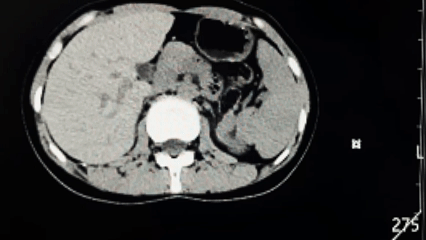

年仅25岁的小玲,因突发腰腹痛就医,被诊断为“双肾积水伴左肾输尿管结石”,病情远比想象中复杂与凶险。进一步的检查揭示了一连串严峻问题:左侧肾脏因结石梗阻,同侧输尿管存在狭窄;右侧肾脏亦出现积水;更特殊的是,她天生患有“马蹄形肾”——一种肾脏融合畸形,这无疑大大增加了诊断与治疗的难度。加之合并“白细胞减少症”,她的身体抵抗力和手术耐受性面临着额外挑战。多重病症叠加,犹如一道道关卡,横亘在这位年轻姑娘的健康之路上。

图片

面对如此复杂棘手的病例,我院泌尿外科团队没有丝毫退缩。科室迅速组织多学科协作,精心研讨,为患者量身定制了缜密的治疗方案。首先为患者进行了对症治疗,改善其免疫力低下问题,待患者免疫力功能改善后,为解除病痛的同时,最大限度保护她未来的肾功能与生活质量,团队决定采用目前先进的经尿道输尿管软镜技术,实施左侧输尿管结石碎石取石术并置入支架管。这一微创方案创伤小、恢复快,但对手术者的技术要求极高,尤其在“马蹄形肾”的特殊解剖结构下,操作更需如履薄冰、精准无误。